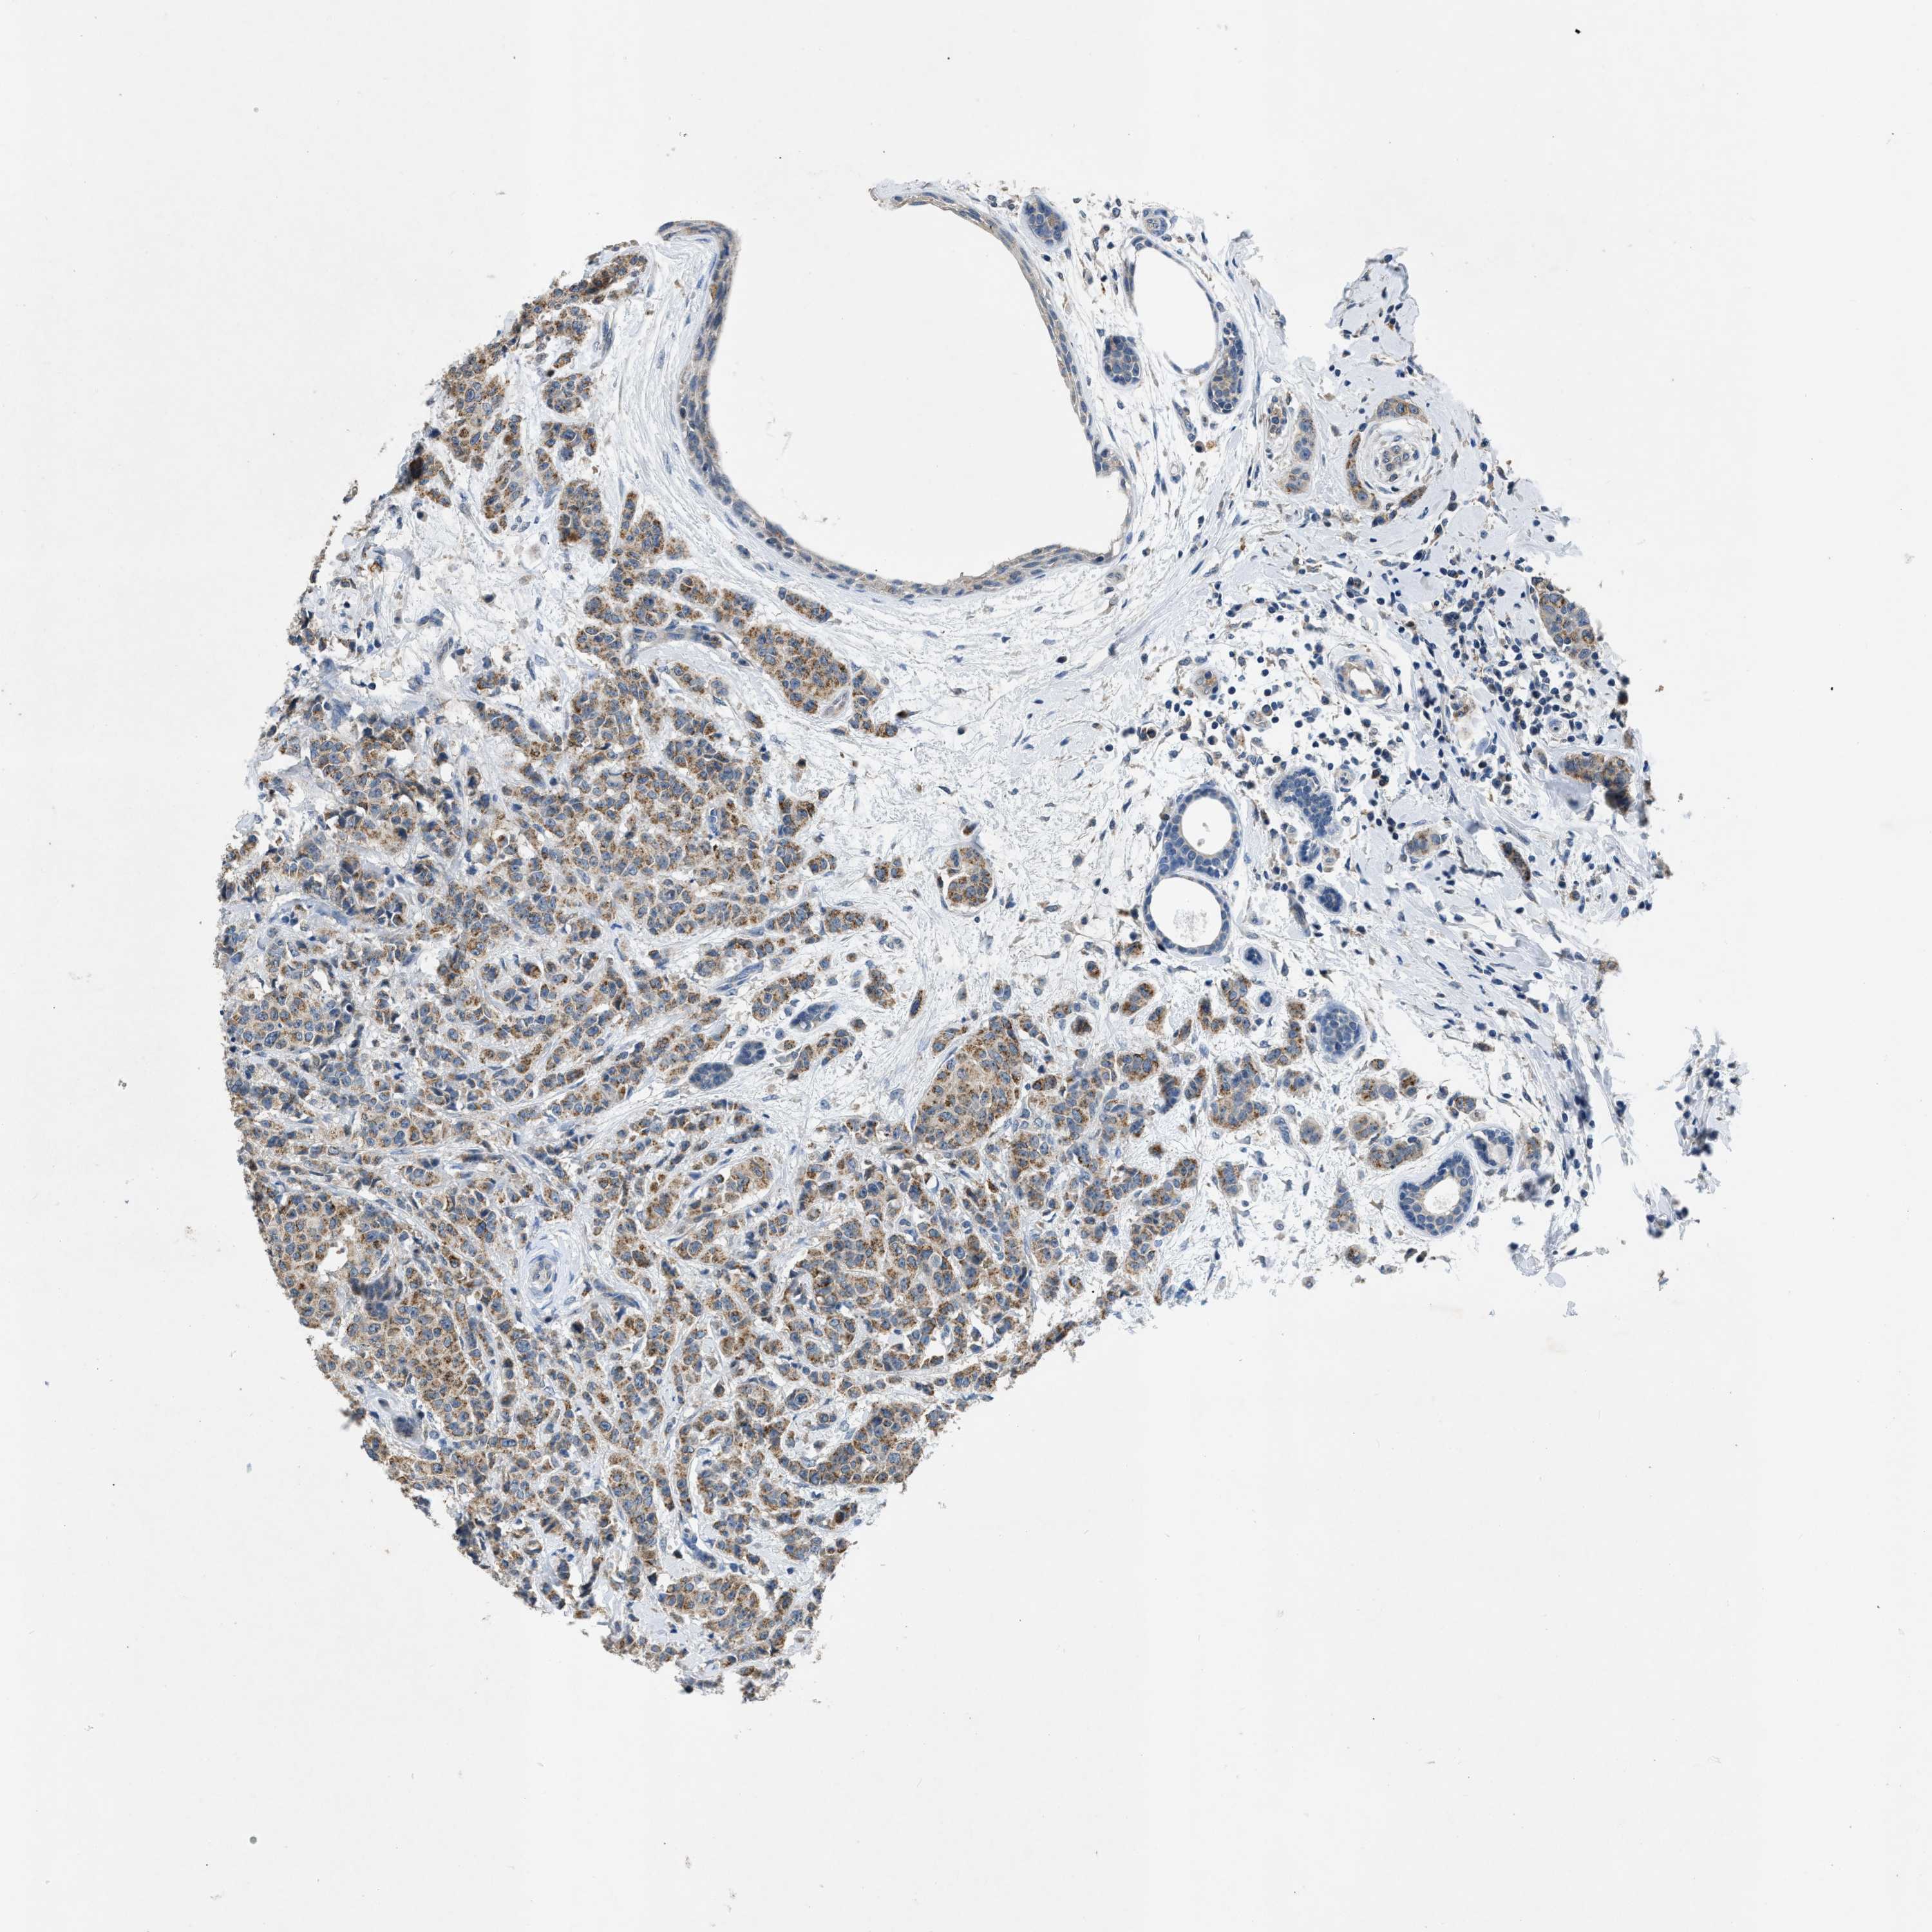

CANCER BREAST CANCER Show tissue menu

BRCA TCGA BRCA VALIDATION PROTEIN EXPRESSION